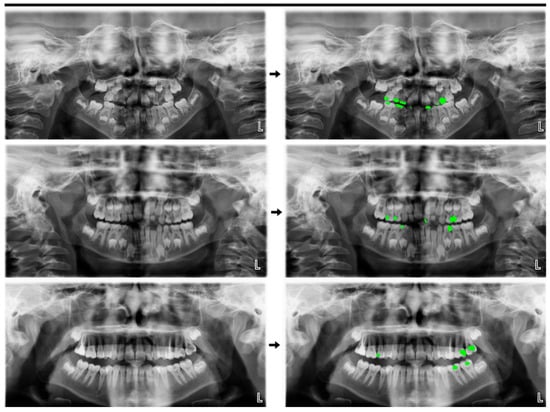

2.5. Model Pipeline

2.6. Total (Primary Dentition + Mixed Dentition + Permanent Dentition)